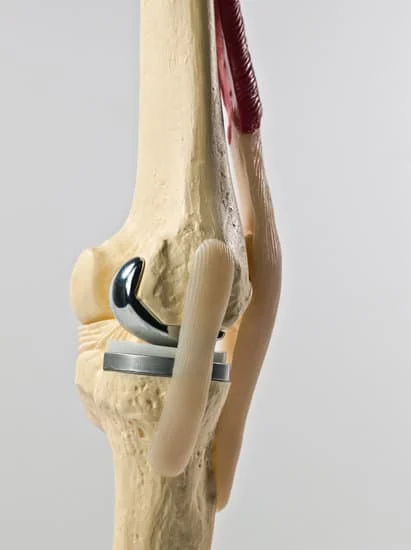

Quality and affordable healthcare has long been the essence in the field of medical sciences & treatment. Every patient expects an early diagnosis and a planned approach to treatment procedures with affordability and access to quality healthcare. Knee replacement, Hip replacement, Fracture treatment are being done by Dr.P.Sankaralingam at very affordable costs without compromising on quality.

• Hip & Knee Replacement and Revision Surgeries